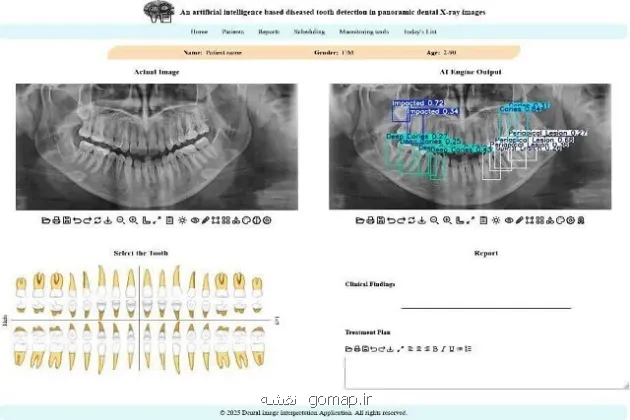

به گزارش نقشه، محققان دانشکدگان فنی دانشگاه تهران، موفق به توسعه یک سامانه هوش مصنوعی شدند که می تواند با تحلیل تصاویر پانورامیک دندان، بیماری های شایعی مانند پوسیدگی، بیماری های لثه و نهفتگی دندان را با سرعت و دقت بالا تشخیص داده و به عنوان دستیار متخصصان، تحولی بزرگ در فرایند تشخیص و برنامه ریزی درمانی ایجاد نماید.

به گزارش نقشه به نقل از ایسنا، به نقل از روابط عمومی دانشگاه تهران، این مطالعه که در چارچوب یک مقاله از رساله دکترای مهدیه دهقانی و با سرپرستی رضا آقایی زاده ظروفی، استاد دانشکده مهندسی برق و کامپیوتر دانشکدگان در یک نشریه بین المللی انتشار یافته است، نشان داده است که این مدل، می تواند به شکل خودکار، محل دقیق ضایعات و ناهنجاری ها را در تصویر شناسایی کرده و احتمال درستی تشخیص خویش را نیز اعلام نماید.

استاد دانشکده مهندسی برق و کامپیوتر دانشگاه تهران با اعلان اینکه در این مطالعه جدید محققان کوشیده اند تا این چالش را با کمک فناوری حل کنند، اضافه کرد: برای این منظور یک سامانه تشخیصی مبتنی بر هوش مصنوعی طراحی شده است که این سامانه، معماری پیشرفته شبکه عصبی به نام YOLOv11 است که آموزش آن بر روی یک مجموعه داده عمومی انجام شده است. این مدل می تواند به شکل خودکار، محل دقیق ضایعات و ناهنجاری ها را در تصویر شناسایی کرده و احتمال درستی تشخیص خویش را نیز اعلام نماید.

ظروفی یکی از نقاط قوت این مطالعه را کاربردی شدن پژوهش در چارچوب یک اپ وب، مطرح کرد و اظهار داشت: یکی از نقاط قوت این تحقیق، کاربردی بودن آن است. این مدل در چارچوب یک اپ تحت وب پیاده سازی شده تا دندان پزشکان و رادیولوژیست ها بتوانند به آسانی از آن بهره گیرند. این سامانه با مشخص کردن محل دقیق مشکلات، به پزشک در اولویت بندی و تصمیم گیری سریع تر کمک می نماید.